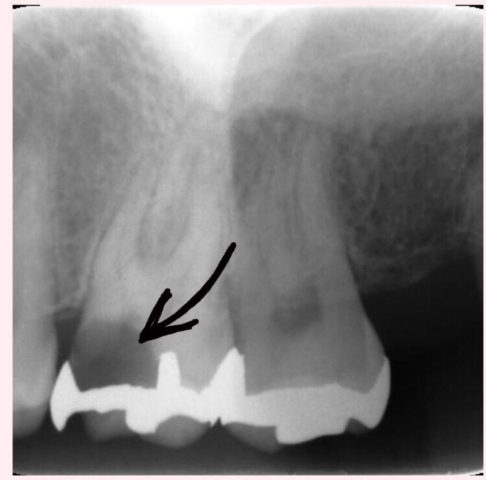

歯の根に細菌が。感染根管治療で徹底洗浄

根管治療について